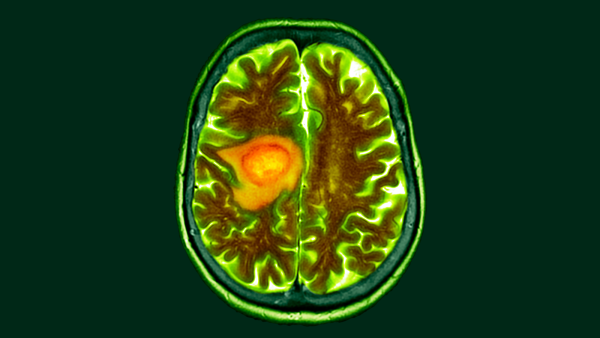

Вчені виявили унікальний спосіб, яким гліобластома раку мозку залежить від серину, амінокислоти. (Зображення: DR P. MARAZZI/SCIENCE PHOTO LIBRARY via Getty Images)

Нове дослідження показує, що зміна в раціоні може зробити смертельну ракову пухлину мозку, гліобластому, більш вразливою до методів лікування раку.

Дослідники, які стоять за цією роботою, вважають, що ця зміна в раціоні використовує ключову метаболічну вразливість раку, і їхня робота демонструє, що цей підхід подовжує виживання мишей, якщо його використовувати в поєднанні з хіміопроменевою терапією.

Здоровим клітинам мозку потрібне паливо для підтримки їхнього широкого переліку функцій, таких як електрична сигналізація та вивільнення хімічних посередників. Ракові клітини позбавляються цих нормальних процесів, перебудовуючись, щоб стати «професійними клітинами, що діляться», — сказав співавтор дослідження Костас Ліссіотіс, професор онкології Мічиганського університету.

Ці зміни викликають великий інтерес у дослідників раку, оскільки вони можуть дозволити методам терапії розрізняти здорові клітини та пухлини, роблячи їх більш цілеспрямованими.

Робота, координована онкологом Мічиганського університету доктором Деном Волом, оцінювала, як гліобластома змінює свій метаболізм у мозку людини та тварин. Дослідження амбітно поєднало лабораторні дослідження та клінічну практику, використовуючи деякі дані з тканин, взятих з мозку пацієнтів, які перенесли операцію з видалення раку. Дослідження вимагало співпраці експертів з хірургії мозку людини та гризунів, метаболічних шляхів та молекулярного аналізу.

Ці екстраговані клітини метаболізували глюкозу, і дослідники відстежували шлях молекул через клітини. У поєднанні з експериментами на мишах, дослідники отримали чітке уявлення про те, що пухлинні клітини роблять по-іншому, коли поглинають цукор.

Здорові клітини метаболізують глюкозу для клітинних процесів, таких як дихання, під час якого цукор і кисень перетворюються на паливо для клітини. Ці клітини також перетворюють глюкозу на амінокислоту під назвою серин, ключовий інгредієнт важливих молекул нейромедіаторів.

Пухлинні клітини, навпаки, відклали ці процеси. Натомість ракові клітини спрямовували глюкозу на вироблення нуклеотидів — будівельних блоків ДНК. Ці молекули є життєво важливими джерелами палива для нескінченної реплікації пухлинних клітин.

Хіміопроменева терапія атакує рак, руйнуючи його ДНК, але таке перенаправлення забезпечує ракові клітини стабільним джерелом нуклеотидів для відновлення пошкоджень. Дослідження показало, що пухлинні клітини також поглинають серин з навколишніх тканин, щоб ще більше стимулювати свій ріст.

Тут Вал та його команда побачили можливість. Вони підготували мишей, яким пересадили ракові клітини людини, до режиму годування, який різко зменшив рівень серину в їхньому раціоні. Ліссіотіс припустив, що це потенційно можна відтворити у пацієнтів з раком, які дотримуються низькобілкової дієти, доповненої протеїновими коктейлями без серину.

Оскільки це зменшило кількість серину, доступного для пухлинних клітин, це змусило рак перенаправити свій метаболізм глюкози назад на виробництво серину. У свою чергу, це скоротило синтез їхніх нуклеотидів і зробило клітини більш вразливими до хіміопроменевої терапії. Миші, які отримували цю комбінацію препаратів, жили довше, ніж миші, які отримували лише хіміопроменеву терапію.

Ліссіотіс пояснив, що ця вразливість, ймовірно, працюватиме обмежений час, оскільки клітини гліобластоми можуть спритно адаптувати свій метаболізм. Крім того, деякі пухлинні клітини, схоже, менше залежать від поглинаного серину, ніж інші. «Якщо ви можете досягти цієї золотої середини, ви позбавляєте їх серину, і ви приходите з терапією, ви отримуєте їх, перш ніж вони знайдуть обхідний шлях», – припустив він.

Вал вже розпочинає роботу над подальшим клінічним дослідженням, щоб підтвердити ці результати на мишах даними, отриманими від пацієнтів з раком у людей.

«Ми сподіваємося запропонувати це нашим пацієнтам пізніше цього року або на початку наступного року», – сказав він. Ця робота також пов’язана з труднощами та координацією. «Лікування раку – це складно. Ми просимо людей щодня проходити опромінення, хіміотерапію. Я думаю, що попросити когось також дотримуватися призначеної дієти може бути складно», – додав він.

Але поточне дослідження надало цінну інформацію, яка стане основою для майбутньої клінічної роботи. «Частково нас радує те, що цей протокол відстеження ізотопів [відстеження міченої глюкози] може сказати нам, які пухлини виробляють серин з глюкози, а які пухлини поглинають серин з навколишнього середовища», — сказав Валь.

Ліссіотіс зазначив, що новаторський метаболічний аналіз, проведений у статті, виявив додаткові зміни в раціоні, які можна було б дослідити в майбутніх дослідженнях. Модифікація серину наразі є найпростішою для впровадження. «Ми вважаємо, що це лише верхівка айсберга», – сказав він.